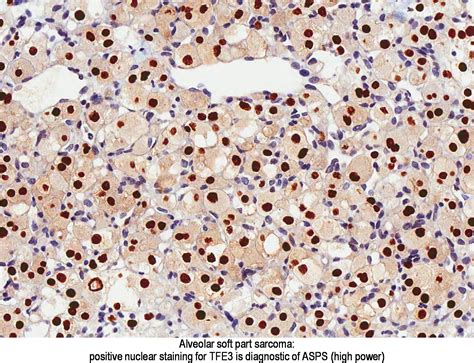

Histopathological examination reveals the characteristic alveolar pattern of ASPS, which is essential for a definitive diagnosis. Additionally, immunohistochemical staining and molecular genetic testing can provide further confirmation.

ASPS is a type of soft tissue sarcoma that originates from the mesenchymal cells, which are responsible for the formation of connective tissues. The disease is named for its distinctive alveolar pattern under the microscope, which resembles the structure of lung alveoli. This pattern is a key diagnostic feature that helps differentiate ASPS from other types of sarcomas.